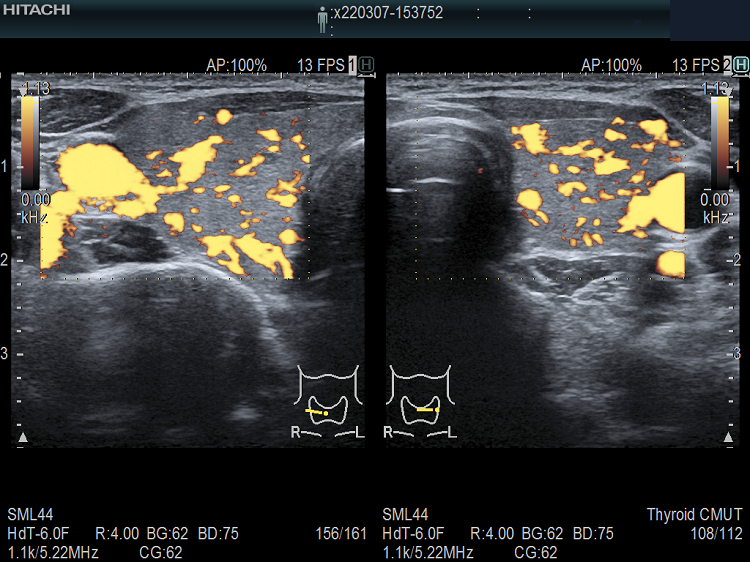

遺伝性甲状腺ホルモン合成障害で、サイログロブリン異常症(サイログロブリン遺伝子異常症)以外は、血中サイログロブリンが上昇するにも関わらず、甲状腺自体の破壊性変化に乏しく、マシュマロ様の軟らかい腺腫様甲状腺腫の形態を取る事があります。

ケース⑤

ケース⑥

ケース⑦

遺伝性甲状腺ホルモン合成障害の超音波(エコー)画像は色々なパターンがあります。

- 常染色体優性遺伝型;腺腫様甲状腺腫の形態になります。